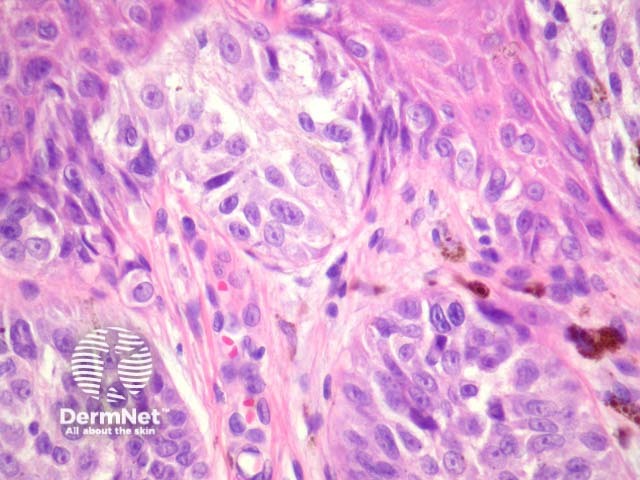

Figure 1